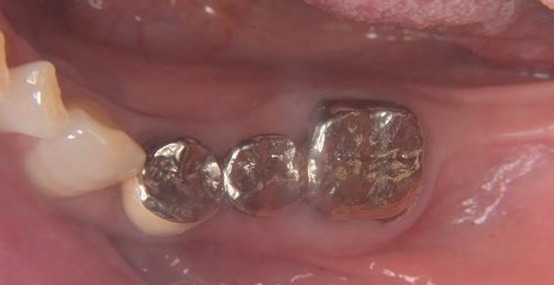

一次手術後(インプラント体埋入後の写真です)

インプラント手術後は大きなトラブルもなく、現在はしっかり咬めて違和感がない状態で経過しています。

上部構造装着後の写真です(スクリュー固定の被せものを装着しています)

インプラントの植立位置を工夫することによって左下の被せものの厚みが確保され、被せものが割れにくい構造にすることができました。

術前の被せものの厚みが薄いという問題点も骨の高さ及びインプラント体を入れる深さを調整することにより十分な被せものの厚みが確保できています。